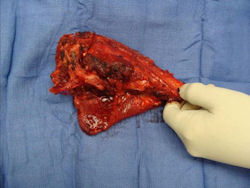

Gross Pathology: Osteosarcoma of Proximal Humerus

- originates from metaphysis of the proximal humerus, extends into surrounding soft tissues

- large soft tissue component that is crossing the glenohumeral joint

- was removed via an extra-articular resection, including scapula (Tikhoff-Linberg resection)

These are examples of the gross pathology specimens of resected conventional osteosarcoma, consisting of both bony and soft tissue areas. X-rays of the specimens are included.

- Osteosarcomas are composed of ossified or non-ossified tissue

- Ossified tissue is yellow-white and hard

- Less ossified tissue is soft and less yellow

- Non-ossified tissue is tan and fleshy

- Most (95%) of conventional osteosarcomas penetrate the cortex and form a large extraosseous soft tissue mass